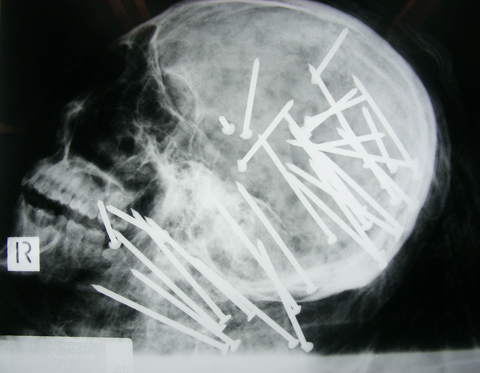

Australian police appealed to the public yesterday for help in solving the gruesome killing of a Chinese man who was shot 34 times in the head and neck with a nail gun before being dumped in a river.

Chen Liu’s badly decomposed body was found in Sydney on Nov. 1, about two weeks after a friend reported him missing, but police have yet to say whether they’ve identified any suspects. New South Wales state police yesterday asked the public to provide any information they may have about the case, releasing graphic X-ray images of the 27-year-old’s skull to highlight the brutality of the crime.

The 34 nails were found during a post-mortem examination of Liu’s body, and were located mainly in his skull.

They were fired from an 85mm nail gun at close range, Beresford said. Police have not recovered the weapon.